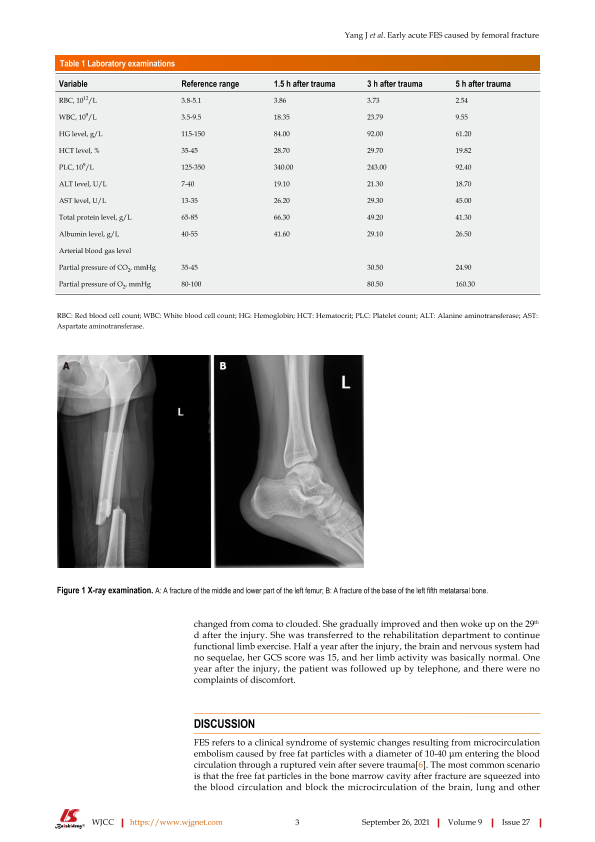

股骨骨折导致的脂肪栓塞病案报道